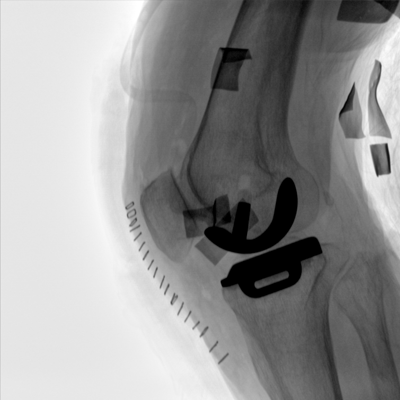

大尺寸動(dòng)態(tài)平板探測(cè)器,高DQE、低噪聲、圖像清晰。采用多分辨率圖像增強(qiáng)處理技術(shù),不同部位不同圖像處理算法,滿足客戶多樣化的需求。

采用智能變頻脈沖透視技術(shù),優(yōu)化圖像質(zhì)量的同時(shí)降低輻射劑量,呵護(hù)醫(yī)患健康